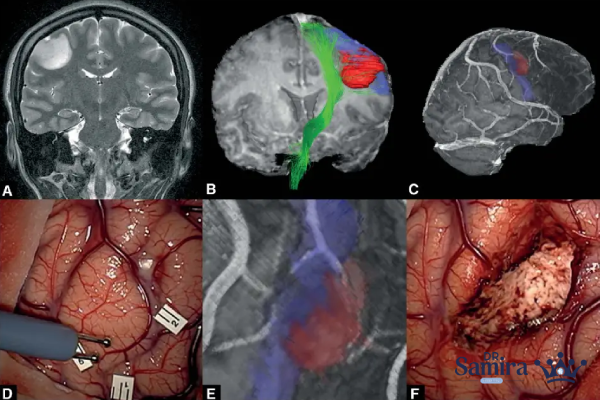

لنفوم مغز چگونه تشخیص داده میشود؟

تشخیص لنفوم مغز نیازمند ترکیبی از آزمایشهای تصویربرداری و بررسیهای تخصصی است. نخستین گام اصولا انجام تصویربرداری MRI است که میتواند وجود تودههای غیرطبیعی را نشان دهد. در صورت مشاهده علائم مشکوک، پزشک ممکن است از بیمار نمونهبرداری (بیوپسی) انجام دهد تا ماهیت سلولها بررسی شود. آزمایش مایع مغزی–نخاعی نیز در بسیاری از موارد کمککننده است و ممکن است سلولهای سرطانی در آن شناسایی شوند. علاوه بر این، آزمایشهای خونی و بررسی عملکرد سیستم ایمنی برای تعیین علت بیماری و انتخاب درمان مناسب ضروری است.

آیا جراحی برای لنفوم مغز استفاده میشود؟

برخلاف بسیاری از تومورهای مغزی دیگر، جراحی نقش محدودی در درمان لنفوم مغز دارد. علت اصلی این است که این تومورها به صورت منتشر رشد میکنند و مرز مشخصی برای برداشت جراحی ندارند. با این حال، در برخی موارد جراحی برای نمونهبرداری یا کاهش فشار داخل جمجمه انجام میشود. بنابراین نقش اصلی جراحی بیشتر تشخیصی است تا درمانی.